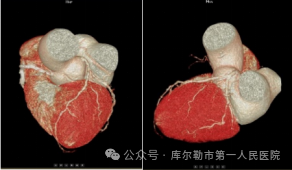

1、无限制心血管成像-单心动周期成像

超高端320排的宽体探测器单圈扫描即可覆盖全心,搭配业内最快转速和独家AI冠脉追焦技术,不管是对于心律不齐,还是高心率等一般CT做不了的心脏检查的情况,超高端320排都能在单心动周期内获得优质图像。真正做到“心跳随意、扫描不止”。同时配合快速扫描和切换扫描方式等技术还可以实现大范围血管联合扫描成像。